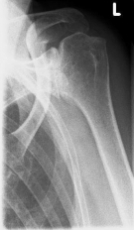

left: X-ray image of an omarthrosis

X-rays can be used to reliably diagnose the extent of joint wear. In the case of severe osteoarthritis, for example, the joint space and the formation of jagged edges (osteophytes) can be detected. If additional damage to the tendons of the shoulder (rotator cuff) is suspected, ultrasound examination (sonography) or magnetic resonance imaging (MRI) can help clarify the situation.